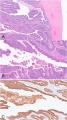

乳腺肿瘤性及非肿瘤性硬化性病变(四)

病种详解之导管内乳头状瘤导管内乳头状瘤的定义,是“发生于导管内的中央型(孤立性)或外周型(多灶性)病变,由伴纤维血管轴心的乳头状突起、被覆上皮细胞构成,且有肌上...